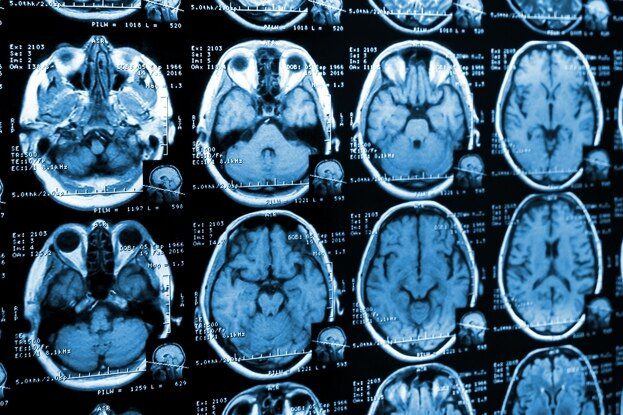

Одна из возможностей заключается в некодирующих модификациях ДНК, упакованных внутри клеток мозга, которые изменяют способ включения и выключения его генов. Исследователи рассмотрели закономерности этих так называемых эпигенетических изменений в области мозга, называемой «зоной Бродмана 9».

Считается, что расположенная в префронтальной коре — передней части мозга, расположенной за лбом, — зона Бродмана 9 (BA9) важна для самосознания и тормозного контроля; двух факторов, которые замешаны в расстройствах, связанных с употреблением психоактивных веществ.